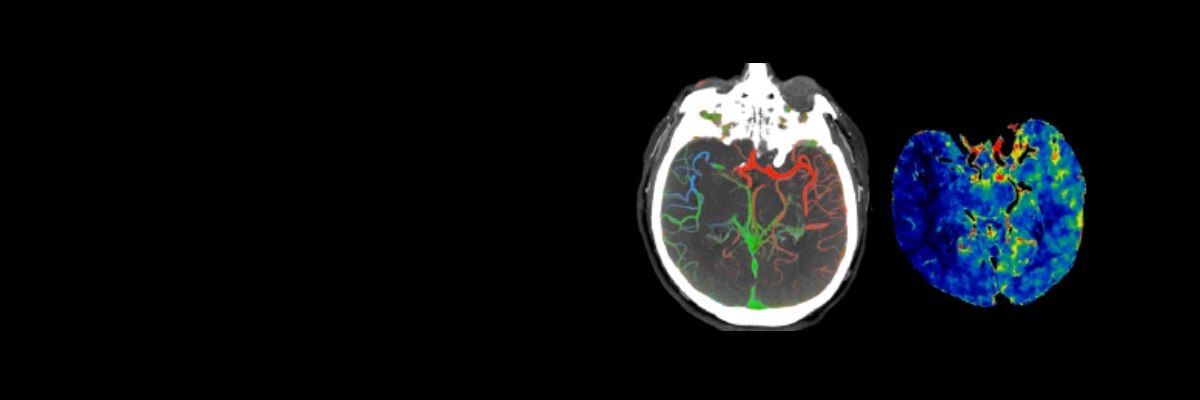

Das System ist in der Lage, Neuroperfusions- und CTA-Untersuchungen des Gehirns in einem einzigen Durchlauf durchzuführen, um umfassende funktionelle und anatomische Beurteilungen zu ermöglichen.

FastStroke CT-Anwendung

Vereinfacht und organisiert CT-Bilder für eine schnelle Beurteilung von Schlaganfallpatienten.